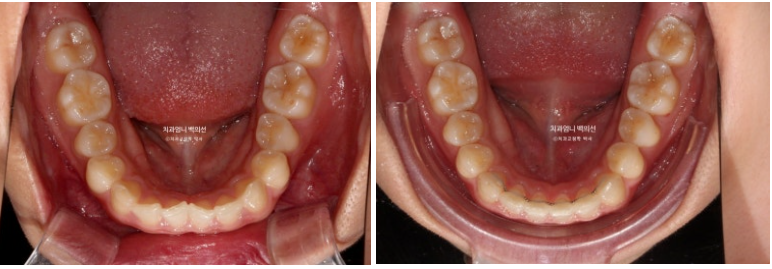

24.03~25.01

24.03

위 앞니 4개가 전반적으로 짧은 편이고 웃을 때 잇몸이 많이 보이는 거미스마일이 있습니다.

잇몸성형으로 거미스마일을 어느정도는 해결할 수 있지만 앞니가 뒤로 쓰러진 옥니이고 깊게 물리는 과개교합도 있고 앞니 사이도 벌어져 있어서 교정을 권유드렸습니다.

어금니교합은 좋습니다.

위 앞니가 아래 앞니를 깊게 덮어 아래앞니가 전혀 보이지 않는 정도의 심한 과개교합입니다.

위 앞니는 정상각도보다 뒤로 쓰러진 옥니입니다

앞니 사이사이에 벌어진 틈도 있습니다.

좋아진 배열과 사라진 틈.

과개교합의 확실한 개선